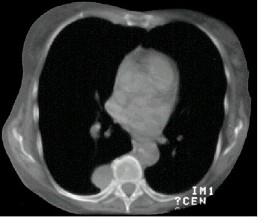

问题 男,67岁,无明显症状,胸片检查发现病变,进一步行CT检查如图,其最可能的诊断为 ( )

选项 A.右下肺炎性假瘤 B.右下肺周围型肺癌 C.右下肺错构瘤 D.后纵隔神经源性肿瘤 E.右侧胸膜间壁瘤

答案 D